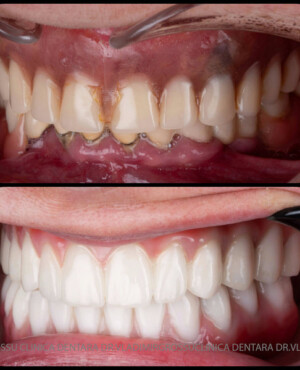

Această metodă este recomandată pacienților edentați total sau celor cu lipsuri dentare multiple. Procedura se realizează într-o singură etapă, iar pacientul primește proteza provizorie în ziua următoare intervenției. De regulă, proteza provizorie este realizată din masă plastică frezată. Suturile se îndepărtează după 5-7 zile.

La aproximativ 6 luni de la prima etapă, pacientul revine pentru protezarea definitivă. În această fază, medicul lucrează la nivelul multiunit-urilor și nu direct pe implanturi, ceea ce reduce riscurile pentru implant în etapa protetică.

Pentru pacienții cu edentație extinsă sau dinți nefuncționali, conceptele All-on-4 și All-on-6 oferă soluții fixe, moderne și eficiente, care asigură estetică, confort și funcționalitate superioară față de proteza mobilă.